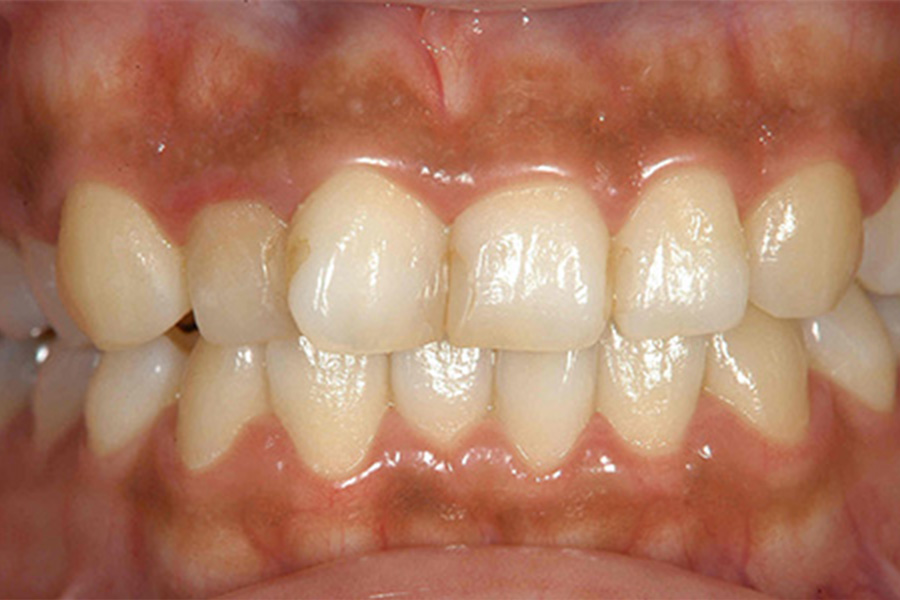

写真の口腔内では、歯ぐきが全体的にやや赤く腫れています。

一見すると、きれいな歯ぐきにみえますが、歯と歯ぐきの境目の歯ぐきが丸く腫れています。また歯と歯のあいだの三角形の形をした歯ぐきも腫れています。